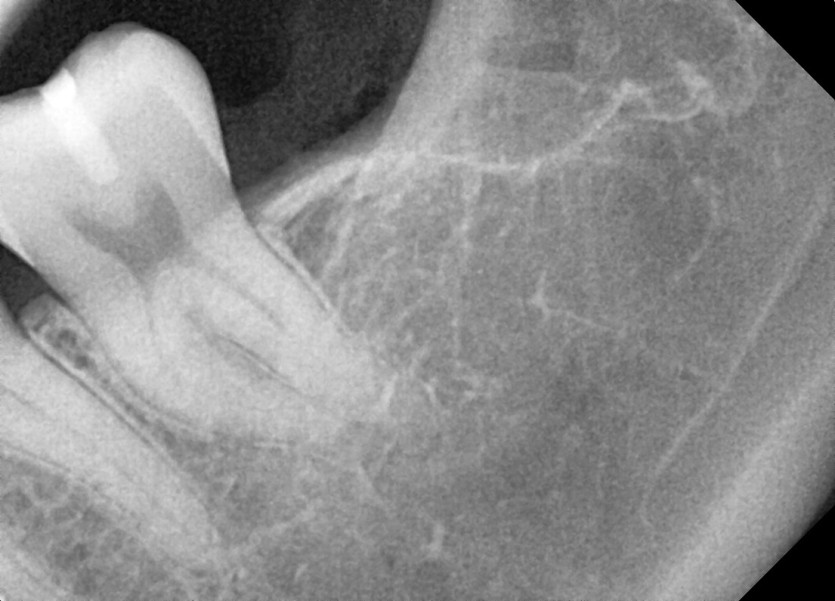

#38,48 사랑니 발치

구강 외과 전문의가 당일 발치했습니다.